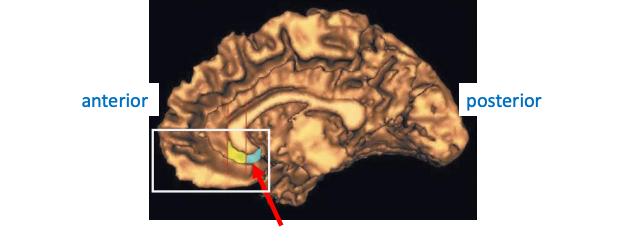

Cellular Disarray of Hippocampus in Schizophrenia

Some schizophrenics have a deficiency of Reelin: A stop signal for migrating cells in hippocampus and prefrontal areas.

Pyramidal neurons in hippocampus are disorganized in schizophrenia.

Hippocampus and amygdala are smaller in some schizophrenics.